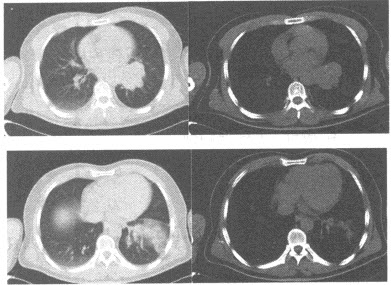

男,56岁,突感胸闷,憋气,就诊后行CTA检查如下图,应考虑为()

A:主动脉瘤

B:主动脉夹层(DeBakeyⅠ型)并主动脉瘤

C:主动脉夹层(DeBakeyⅡ型)并主动脉瘤

D:主动脉夹层(DeBakeyⅢ型)并主动脉瘤

E:主动脉血栓